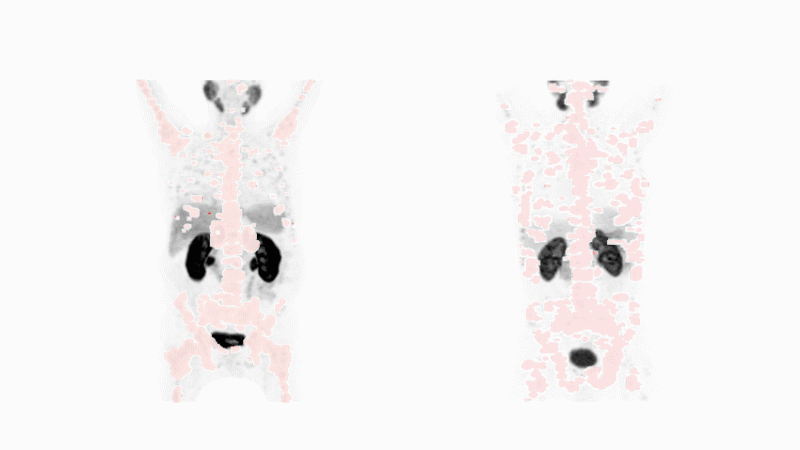

snmmi-animated-nuclear-medicine-image

核医学には診断的な要素があります。治療薬と同じ腫瘍特異的分子を使用して、がんを明らかにする可能性のある放射性原子を送達するものです。これらの原子は、特殊な画像装置によって検出されるガンマ線を放出します。この薬で特定のがんが見つかれば、たとえ外科医が見ることも切除することもできないような小さな点でも、全身のどこにあっても、この方法によってそのがんが明らかになります。画像:Michael Hofman 提供 Journal of Nuclear Medicine.Fidelis Onwubuekeによるアニメーション

核医学にも診断的要素があります。診断は治療薬と同じ腫瘍特異的分子を使用して、がんを明らかにする可能性のある放射性原子を送達します。

この原子が発するエネルギーは、体外の画像スキャナーで検出することができます。このような放射線は、体のどこに広がっていても、医師ががんを見ることを可能にします。

この診断では、分子パズルのピースが一致した場合にのみ、患者のがんが明らかになります。もしそうであれば、同じ腫瘍特異的分子を用いた標的放射性物質治療が、患者さんに適している可能性があります。

この 「見て、治す」 能力により、医師は患者さんのがんの種類に応じて適切な薬を選択することができるようになりました。さらに、今後のスキャンによって、医師は治療の進行に伴って薬が効いているかどうかを判断することができます。